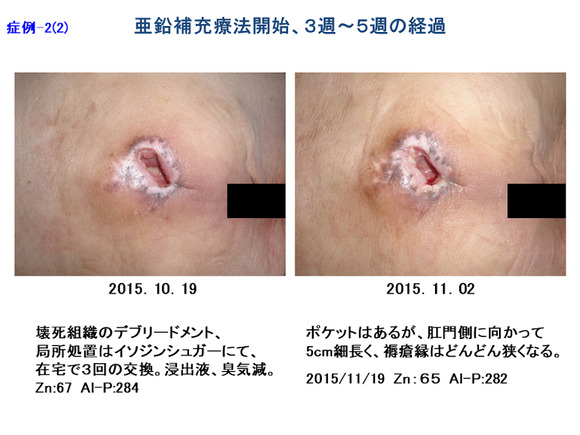

褥瘡の「創縁」「創面」の性状を把握しよう 2ページ目 :日経DI。

⑤深い褥瘡攻略の道標 ”TIME+α”のE 創部辺縁の段差 :難関攻略!褥瘡ポケットを治す秘策とは!? -皮膚科専門医が伝授!医療従事者のための高齢者皮膚トラブル対策講座。

褥瘡のポケット形成について - 東御市民病院・東御市立みまき温泉診療所・東御市立助産所とうみ。

褥瘡のポケット形成について - 東御市民病院・東御市立みまき温泉診療所・東御市立助産所とうみ。